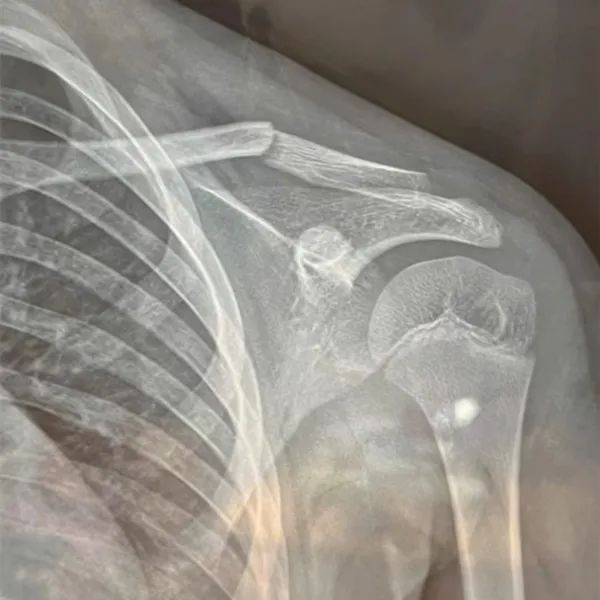

经过医院诊断

事故导致孩子左侧锁骨中外段骨折

需要长时间休息静养